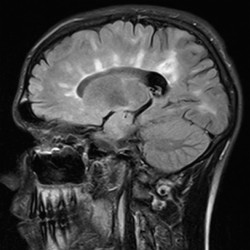

- MRI imaging with contrast is the most important imaging modality in the workup of possible MS.

- Demyelinating lesions related to MS are ovoid, >3 mm in diameter, and are typically located in particular regions: periventricular (Dawson’s fingers), juxtacortical, cortical, or spinal cord.